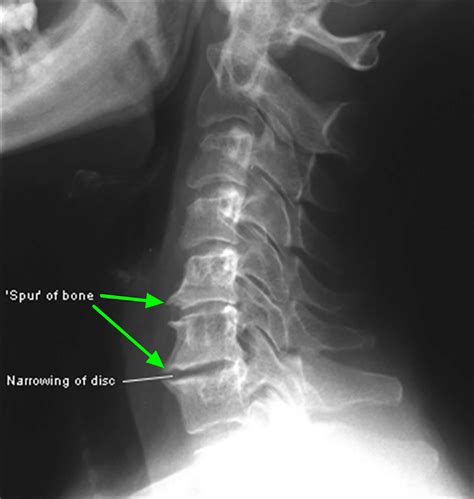

Calcaneal spur anatomy foot problem diagnostic and treatment in ...